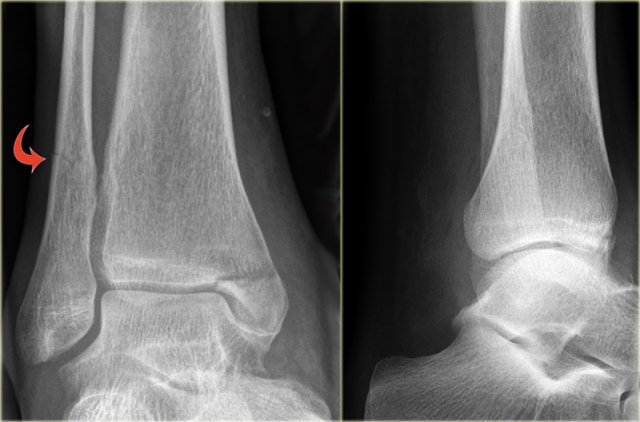

Weber C fracture - at least stage 3 Weber C fracture - at least stage 3

Here an example of a Weber C fracture with a proximal fibula fracture.

Notice that on the radiograph of the ankle no fracture is seen.

You might misdiagnose this as only some soft tissue swelling.

In fact this is an unstable ankle fracture, since there also must be a rupture of the medial collateral ligament (stage 1) , so the ring is broken in two places leading to instability.

According to Lauge Hansen we are probably dealing with:

1. Medial collateral band rupture

2. Rupture of the anterior syndesmosis

3. High fibula fracture

4. and possibly a rupture of the posterior syndesmosis

Stage 4

Finally the posterior syndesmotic ligament ruptures, or there is an avulsion of the posterior malleolus, also known as posterior malleolus fracture (red arrow).

The medial clear space is only slightly widened, but based on the stages of Lauge Hansen there must be a collateral band rupture.